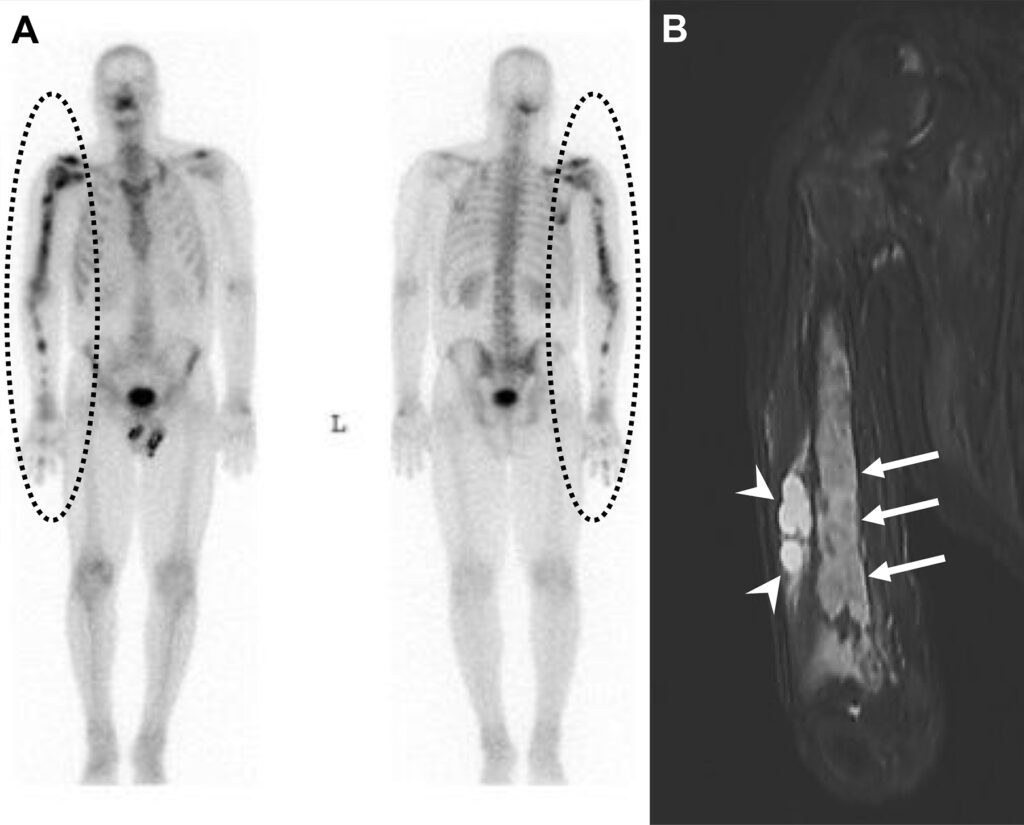

Malattia metastatica con pattern miliare in una donna di 44 anni con carcinoma papillare della tiroide.

L’esame total body rileva una tenue ipercaptazione diffusa e simmetrica a livello di entrambi i campi polmonari. Si tratta di una captazione extra-ossea anomala del radiotracciante osteotropo. L’imaging morfologico dell’Rx conferma la presenza di una massiva disseminazione metastatica polmonare, caratterizzata da innumerevoli e minuscoli noduli bilaterali (il classico “pattern miliare”), più addensati alle basi. Il tecnezio difosfonato (99mTc-MDP) può accumularsi in lesioni metastatiche extra-ossee, come quelle polmonari derivanti da alcuni tumori (tra cui il carcinoma tiroideo, mammario o osteosarcoma). Questo fenomeno è spesso dovuto alla presenza di microcalcificazioni all’interno del tessuto neoplastico o ad alterazioni del metabolismo locale del calcio.